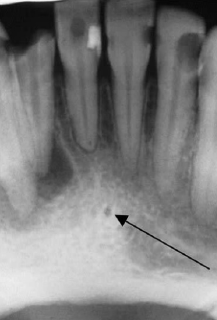

46. What is showing by arrow?

Genial Tubercles (Mental Spine) bony protuberances located on the lingual surface of the mandible slightly above the inferior border and in the midline. serve to attach the genioglossus muscles (at the superior tubercles) and the geniohyoid muscles (at the inferior tubercles) to the mandible. Usually well visualized on mandibular occlusal radiographs as one or more small projections.